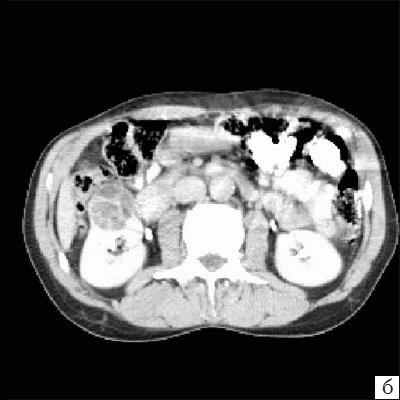

(Слева) КТ с контрастированием, аксиальная проекция: инкапсулированное многокамерное кистозное образование, выступающее в ворота почки, с перегородкой, накапливающей контраст. Наличие капсулы вокруг кисты — отличительная черта, позволяющая отличить мультилокулярную кистозную нефрому от других поликистозных образований почки.

Достоверность комьютерной томографии (КТ) в диагностике мультилокулярной кистозной нефромы, по данным разных авторов, составляет от 95 до 98%. При КТ определяется негомогенное многокамерное образование округлой или неправильно-округлой формы, возможно с капсулой, плотность образования неоднородная, пониженная относительно паренхимы, в полости образования определяется большое количество перегородок (рис. 3). Если при КТ с контрастированием происходит накопление контрастного вещества, это может быть признаком предполагаемой малигнизации [11, 13, 19].

а) До внутривенного контрастирования определяется негомогенное образование неправильной округлой формы с капсулой и едва заметными перегородками, плотность ниже, чем плотность паренхимы почки.

б) После контрастирования отчетливо выявляются плотная стенка и множество перегородок.